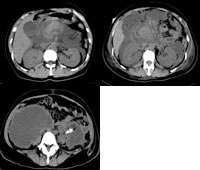

入院后查血常规提示:白细胞计数(WBC) 13.8×109/L、GRAN 85.4%。急诊生化:Na+ 127.5 mmol/L、K+ 3.16 mmol/L、Ca2+ 1.92 mmol/L。血淀粉酶 246 U/L。血脂检查:胆固醇 20 mmol/L,甘油三酯36.1 mmol/L。腹部CT结果提示,胰腺增大、肿胀、边界模糊。

予以禁食、抑制胰酶分泌、抗炎、降脂、补液及对症治疗 ......